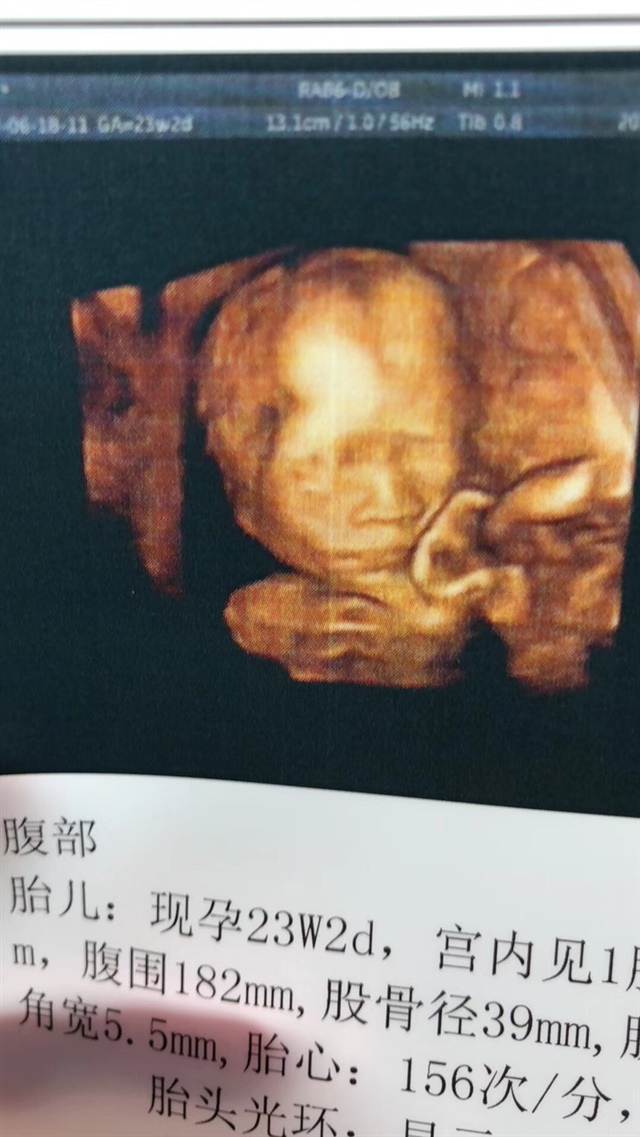

产前检查 B超